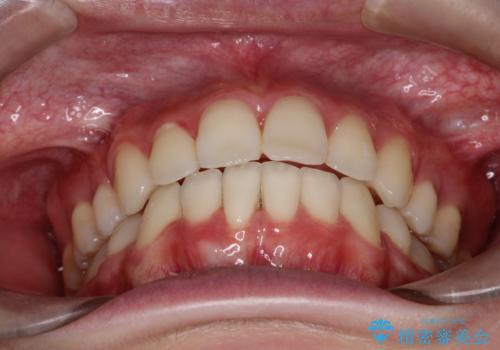

抜歯矯正により、前歯をしっかり下げることで口元がすっきりしました。

- 前歯が出ているため口が閉じにくく、横顔が気になるとのことで来院された患者様です。。

上下の前歯が前方に傾斜しており、口唇の突出感がありました。

上下左右の前から4番目の歯を抜歯して、上下の前歯を後方に移動させる計画としました。